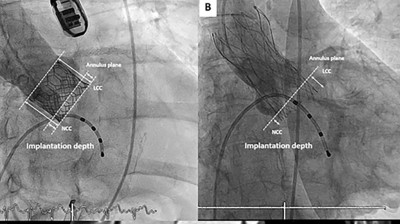

Chirurgische Transkatheter-Aortenklappenexplantation

• TAVI

• Übersichtsartikel

Mit dem rasanten Anstieg der Transkatheter-Aortenklappenimplantationen (TAVR) ist auch die Zahl der notwendigen Reinterventionen stark gewachsen. Insbesondere die herzchirurgische Explantation von TAVR-Prothesen (engl. Explant-TAVR) entwickelt …

Transkatheter Aortenklappenimplantation (TAVI)/© Boonyakiatwattana W. et al. doi.org/10.1186/s12872-022-02576-y unter CC-BY 4.0, Echokardiografie der Aortenklappe/© Pitchy / stock.adobe.com, Schmerzende livide Areale am Bauch/© A. Frahnert, Aneurysma bei 2-monatigem Säugling mit Kawasaki-Syndrom/© Navidi et al. https://doi.org/10.1186/s13256-024-04987-1 unter CC-BY 4.0, Kanüle für Katheterbehandlung/© romaset / stock.adobe.com, Ärztin führt eine Nierenultraschalluntersuchung durch/© Graphicroyalty / stock.adobe.com (Symbolbild mit Fotomodell), Patient mit perforierter ICD-Tasche/© P. Fleckenstein, Vegetationen der Herzklappe/© Schönfeld L et al. / all rights reserved Springer Medizin Verlag GmbH, Echokardiografische Evaluation der Aortenklappeninsuffizienz/© Digitales Archiv der Uniklinik Köln, Explantierte Prothese nach Transkatheter-Aortenklappenimplantation/© Saha S et al. / all rights reserved Springer Medizin Verlag GmbH, Mitralklappe/© Springer Medizin, Hauteffloreszenzen der rechten Hand/© Marschner M et al. / all rights reserved Springer Medizin Verlag GmbH, Search Icon, Eine ältere Frau riecht an einem Basilikumblatt/© Halfpoint / Stock.adobe.com (Symbolbild mit Fotomodell), Ultraschall bei einem älteren Patienten/© Alex Potemkin / Getty Images / iStock (Symbolbild mit Fotomodellen), Person hält Tablette und Glas/© bilderstoeckchen / stock.adobe.com (Symbolbild mit Fotomodell), EKG befunden mit System - EKG Essential/© Springer Medizin Verlag GmbH